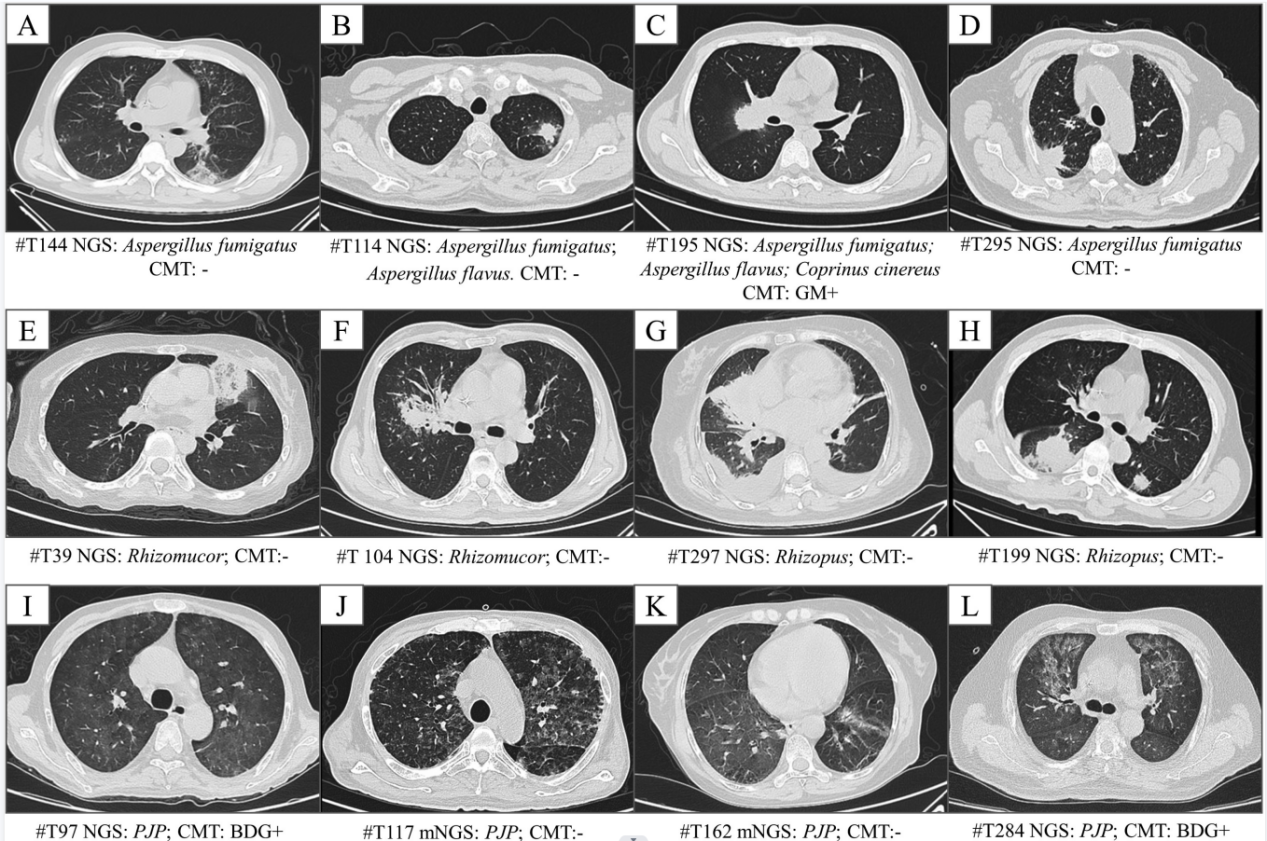

随后,研究者对血液样本病原mNGS检测在疑似肺部真菌感染患者中的诊断价值进行分析。结果显示,曲霉、毛霉、肺孢子菌这三种血液病患者肺部感染最常见的真菌病原,检出率分别为14.2%、8.1%和5.0%。其中粒缺患者曲霉检出率高于非粒缺患者,检出曲霉的23名患者中,传统微生物学检测仅检出10名患者。对检出真菌的46名患者,临床医生对其半数以上进行了药物调整,优化了抗真菌感染治疗策略。